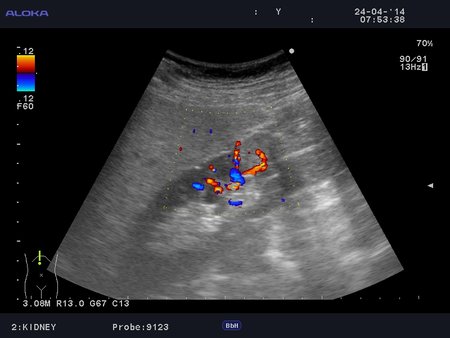

Онкоцитома почки - УЗИ

Женщина 76 лет. Жалоб не предъявляет.

t6_20140424_KIDNEY_0016.JPG

t6_20140424_KIDNEY_0011.JPG